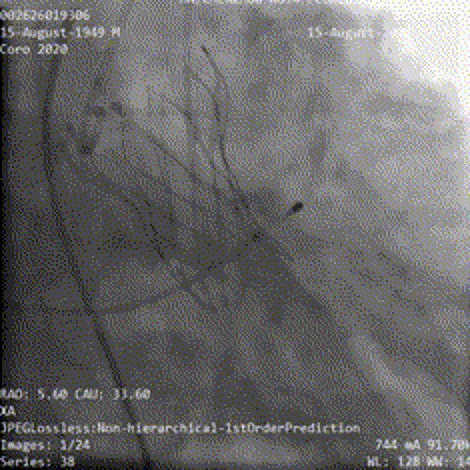

瓣膜释放到工作位后造影显示瓣膜流入端压缩较明显,瓣膜位置良好,冠脉显影正常,脱钩后瓣膜形态、位置良好,少量瓣周漏,弓部造影未见明显异常;

工作位造影

瓣膜释放脱钩

最终造影

弓部造影